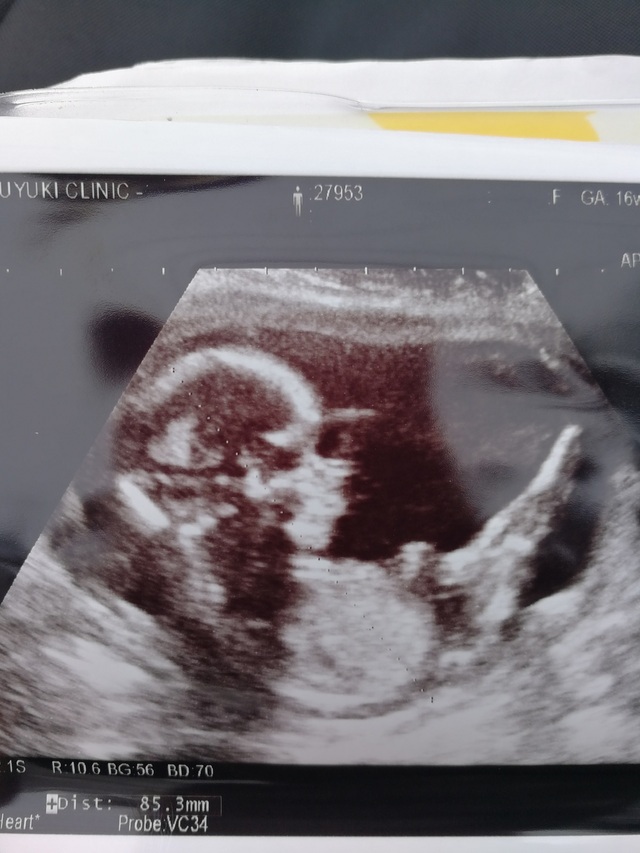

16週6日(16w6d・男の子)|keiichi さん(32歳)

エコー写真撮影時のエピソード:

待ちに待った安定期。前回の診察から間があいたのでドキドキしながらエコーに臨んだら、背骨がくっきり見えました!たまたま母と一緒に診察に行った日で、初孫のエコーに母がはしゃいでいたのを良く覚えています。帰ってから写真を見せたら、パパも大喜びしていました。